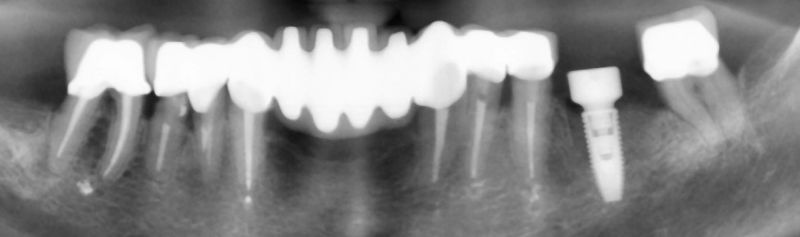

Много често това е трудно постижимо или направо невъзможно. Тогава идва на помощ дигиталното проектиране за точна позиция на зъбния имплант, подготвителната костна аугментация с костозаместителни присадки и използването на хирургичните водачи за точно поставяне на зъбните импланти. Хирургичните водачи са също дигитално проектирани и техният проект се прави едновременно с проекта на зъбните импланти. Технологично те се изработват чрез 3D принтиране и представляват прозрачни шини с метални канюли в тях, през които преминават различни по диаметър дрилове за препариране на имплантната ложа, а накрая и самото поставяне на зъбния имплант.

В случаите, когато имаме много на брой зъбни импланти /повече от три/. То тогава най-често зъбните импланти се поставят в тяхната хирургична позиция с помощта на хирургични водачи, а протетиката се осигурява от специални надстроики /абатмънти/, наречени multi unit.

Такава е методиката All on 4 на Nobel Biocare и Пало Мало за лечение при пълно обеззъбяване с помощта на зъбни импланти.